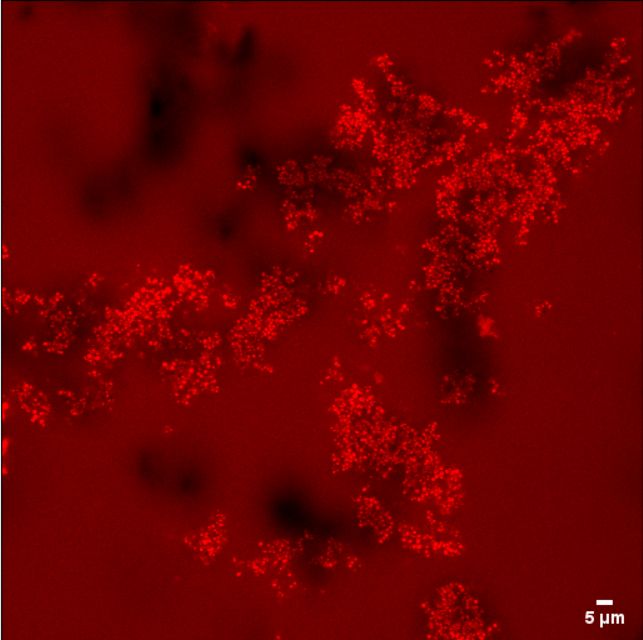

Laura Confalonieri, University of Edinburgh

From friendly skin flora to a dreadful pathogen

Confocal laser scanning microscopy image (Leica TCS SP8) of Staphylococcus Epidermidis RP62A biofilms, grown in vitro in human plasma on a plastic surface (Ibidi), fluorescently stained with C-SNARF-4 (Thermo Fisher). S. epidermidis is a friendly bacterium which inhabits the skin of virtually all humans but is also a major cause of hospital-acquired infections associated with implanted medical devices. This research, which applied experimental and computational techniques to study infection in central venous catheters, was initiated in collaboration with Kimal, a leading UK manufacturer of medical devices, to address the problem of detecting the risk of lethal bloodstream infections such as sepsis.